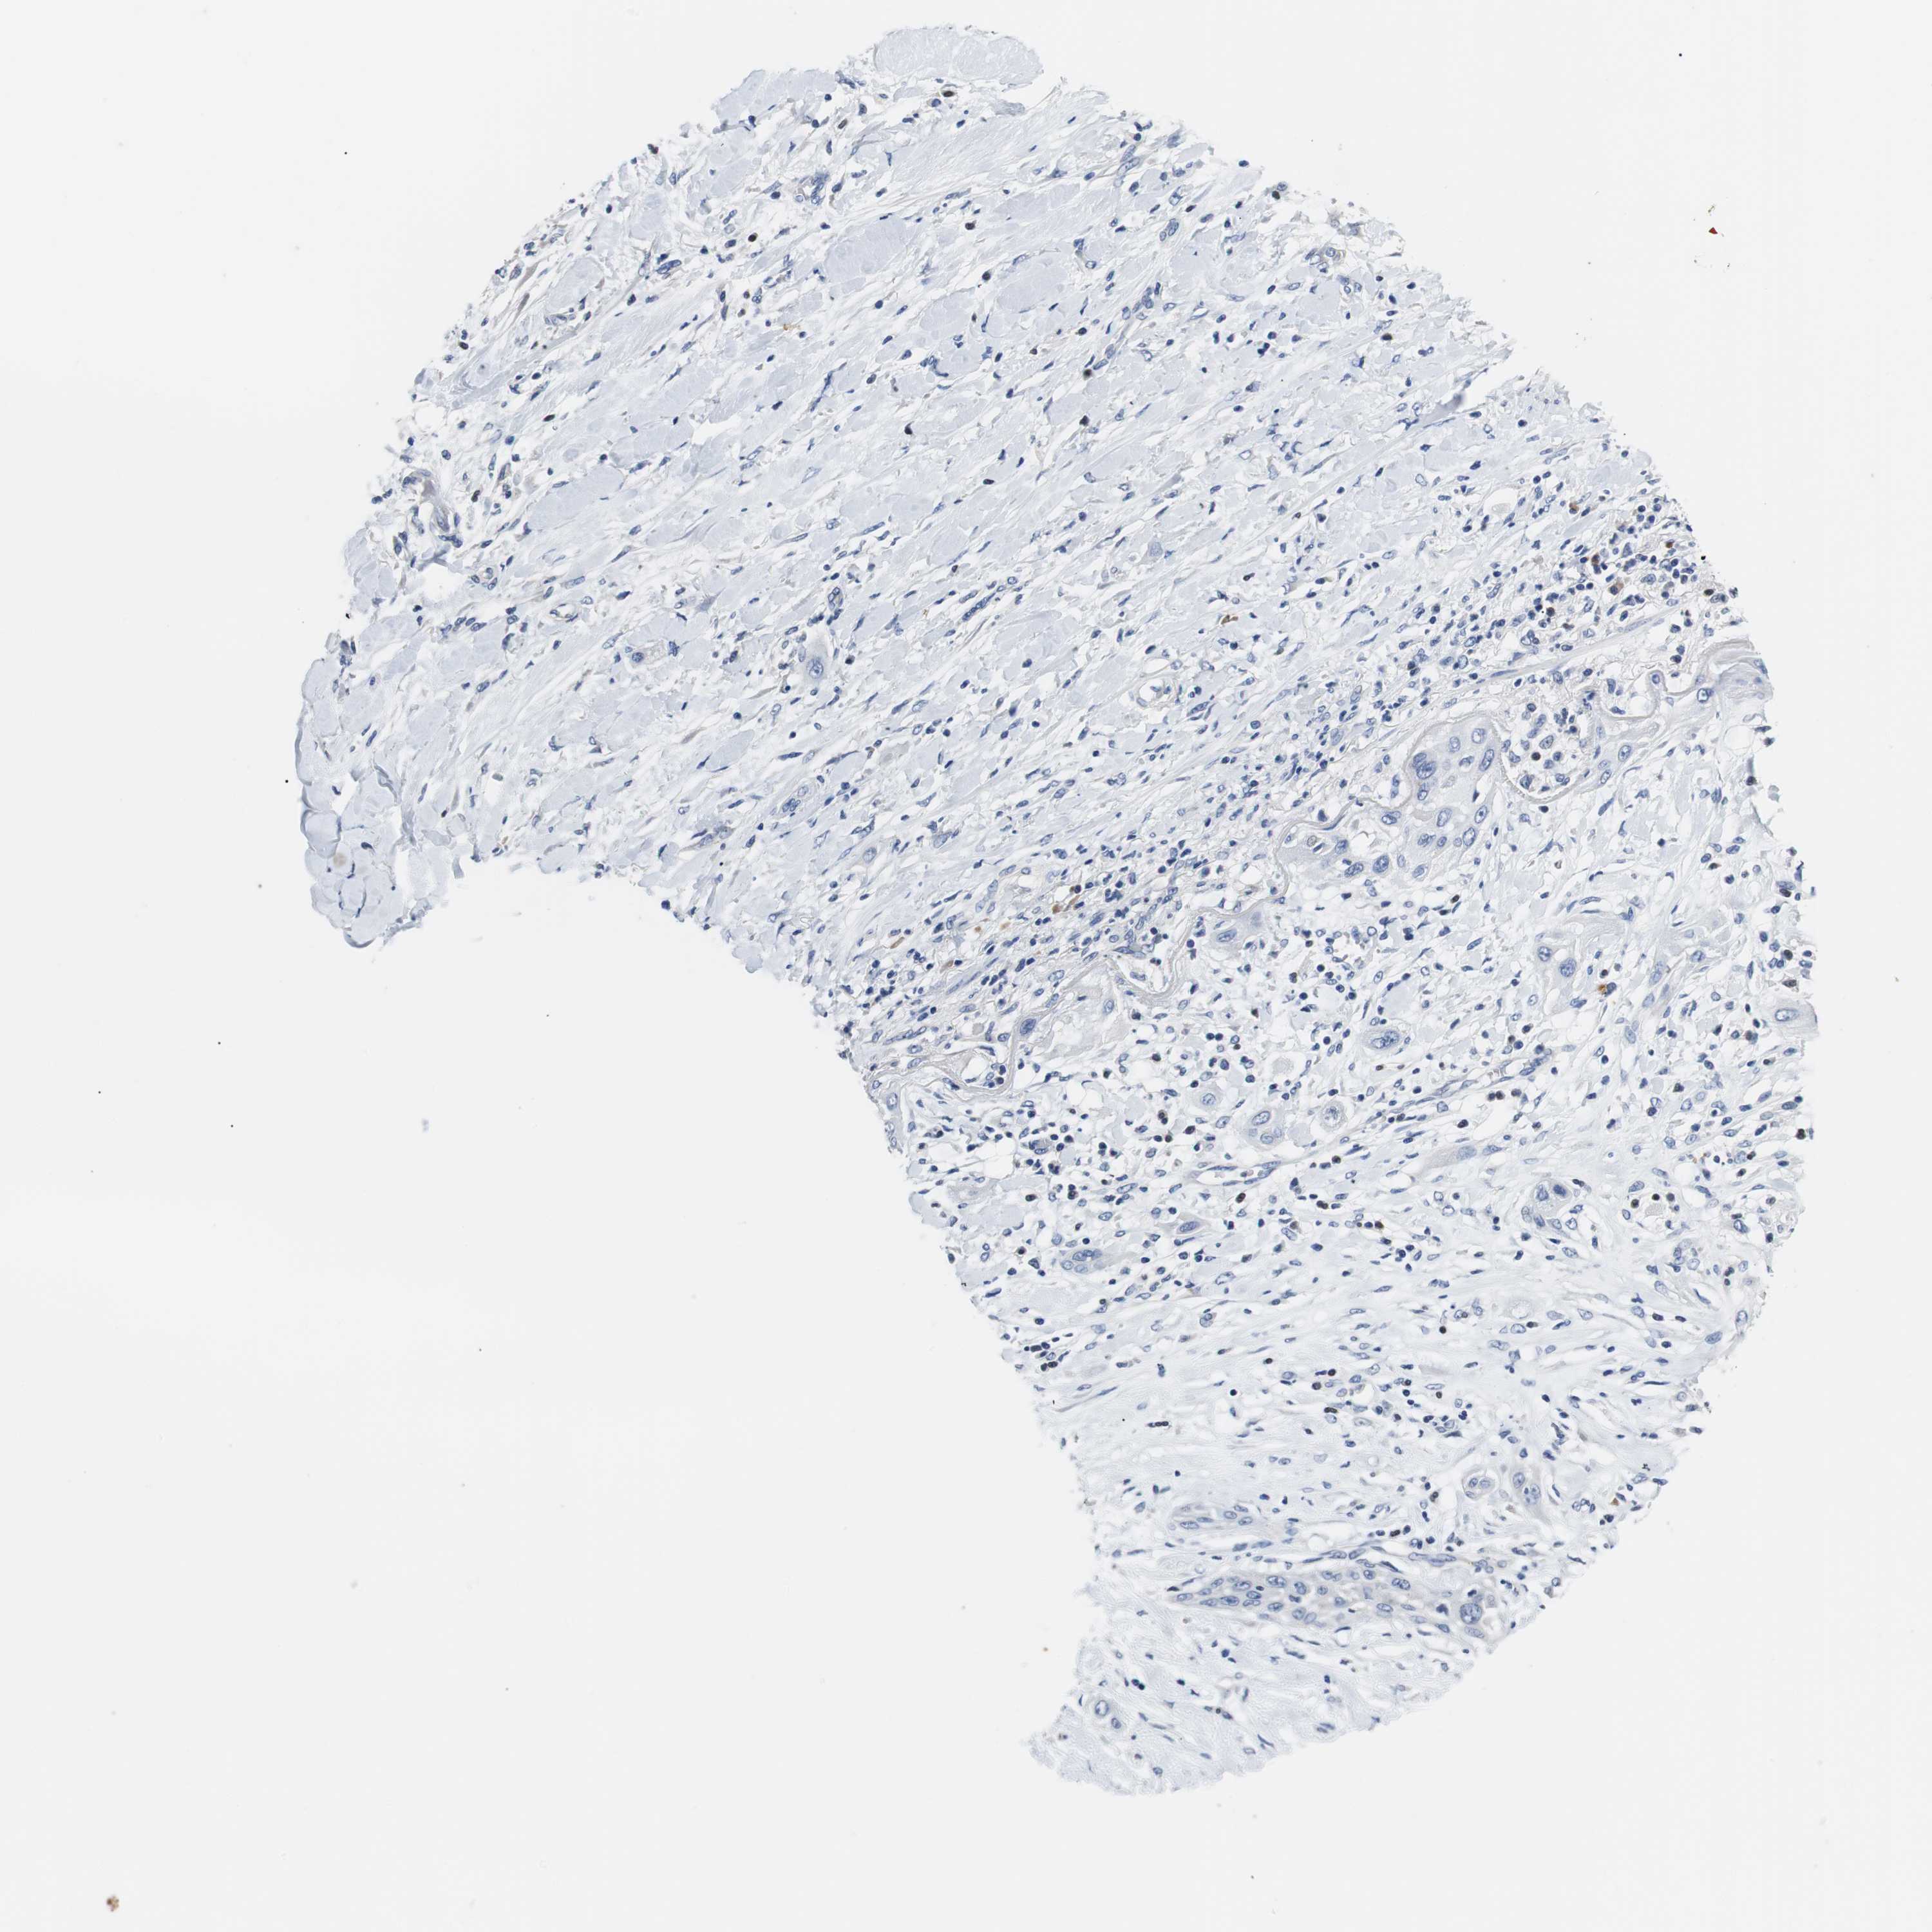

LUNG ADENOCARCINOMA (TCGA) - Interactive survival scatter ploti

The Survival Scatter plot shows the clinical status (i.e. dead or alive) for all individuals in the patient cohort, based on the same data that underlies the corresponding Kaplan-Meier plots. Patients that are alive at last time for follow-up are shown in blue and patients who have died during the study are shown in red.

The x-axis shows the expression levels (FPKM) of the investigated gene in the tumor tissue at the time of diagnosis. The y-axis shows the follow-up time after diagnosis (years). Both axes are complimented with kernel density curves demonstrating the data density over the axes. The top density plot shows the expression levels (FPKM) distribution among dead (red) and alive patients (blue). The right density plot shows the data density of the survived years of dead patients with high and low expression levels respectively, stratified using the cutoff indicated by the vertical dashed line through the Survival Scatter plot. This cutoff is automatically defined based on the FPKM cutoff that minimizes the p-score. The cutoff can be changed by dragging the vertical line or by entering a cutoff value in the square labeled "Current cut-off".

Under the Survival Scatter plot the p-score landscape (black curve; left axis) is shown together with dead median separation (red curve; right axis). Dead median separation is the difference in median mRNA expression between patients who have died with high and low expression, respectively. It is calculated as follows: median FPKM expression of dead patients with high expression - median FPKM expression of dead patients with low expression. This is intended to aid the user in visually exploring custom cutoffs and the associated p-scores and dead median separation.

Individual patient data is displayed and can be filtered by clicking on one or more of the category buttons on the top of the page. Categories describing expression level and patient information include: high, low, alive, dead, female, male and tumor stages. The scale of the x-axis can be toggled between linear and log-scale by clicking on the "x log" button. Mouse-over function shows TCGA ID, patient information and mRNA expression (FPKM) for each patient.

& Survival analysisi

Kaplan-Meier plots summarize results from analysis of correlation between mRNA expression level and patient survival. Patients were divided based on level of expression into one of the two groups "low" (under cut off) or "high" (over cut off). X-axis shows time for survival (years) and y-axis shows the probability of survival, where 1.0 corresponds to 100 percent.

PCK1 is not prognostic in Lung Adenocarcinoma (TCGA)